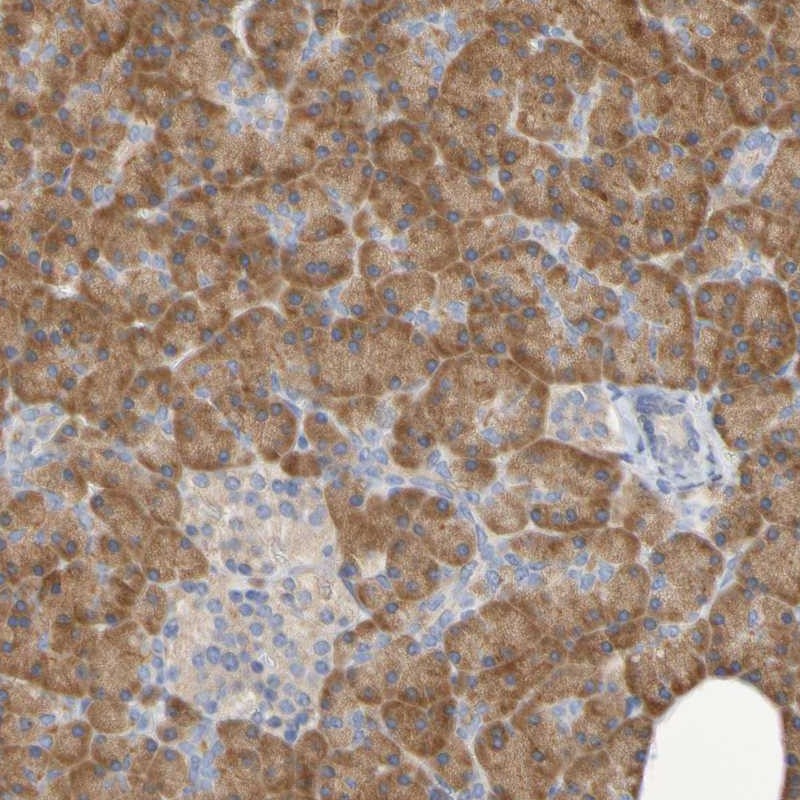

Immunohistochemical staining of human pancreas shows strong cytoplasmic positivity in exocrine glandular cells.